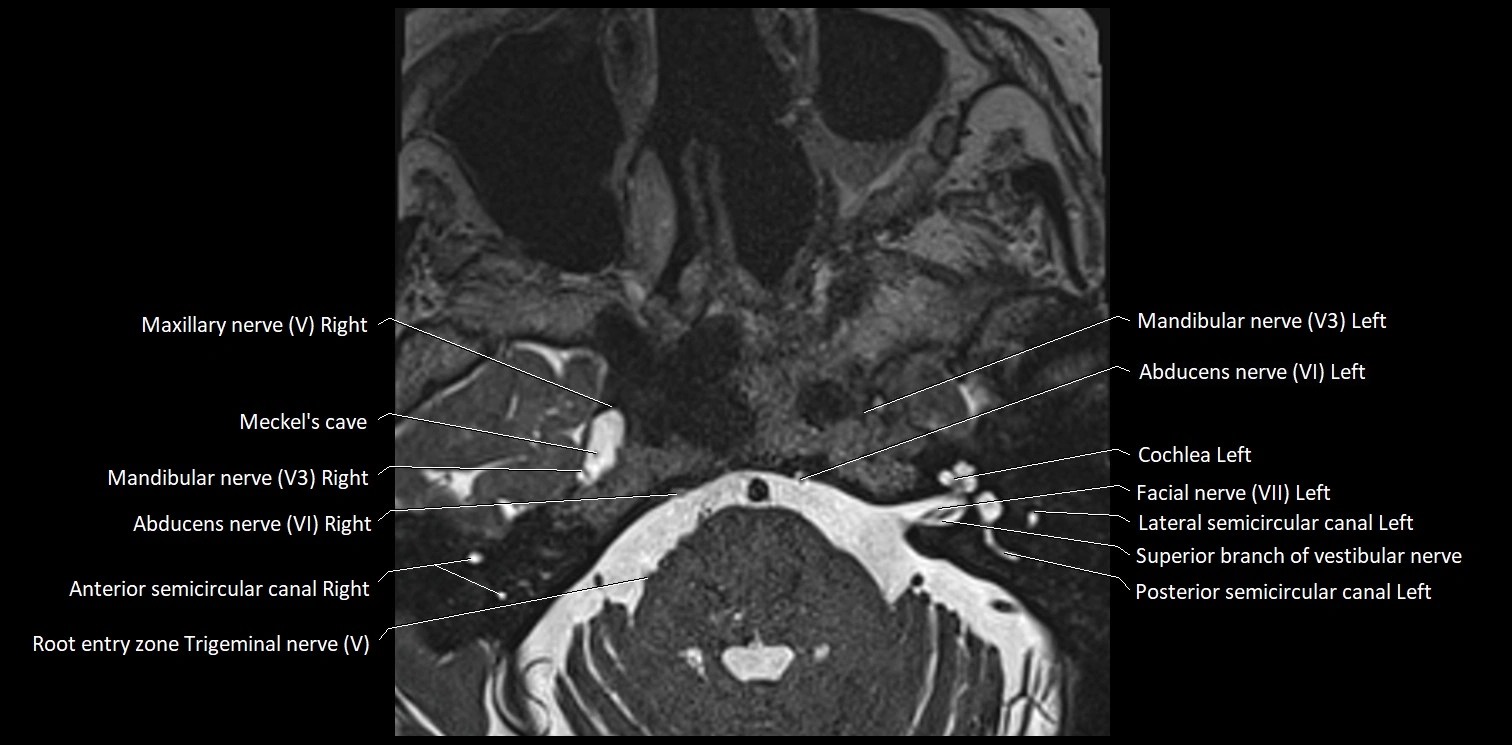

MRI Appearance

• The abducens nerve is a small, thin, linear structure

• Best visualized on high-resolution T2-weighted 3D MRI sequences (e.g., FIESTA or CISS)

• Seen as a hypointense (dark) line running from the brainstem at the pontomedullary junction, traversing the prepontine cistern, and entering Dorello’s canal under the petrosphenoidal ligament, then into the cavernous sinus, and finally the orbit

• May be challenging to visualize in standard MRI due to its small size

• Pathology may be inferred by absence, displacement, or enhancement of the nerve